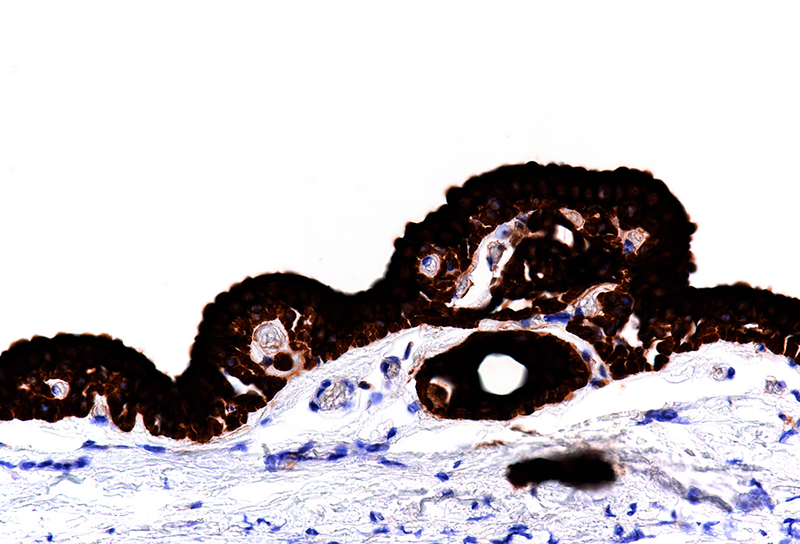

Histological examination disclosed a hybrid cyst lining epithelium, composed of a luminal layer of columnar cells with slightly basophilic cytoplasm and signs of mucin production, while slightly darker cuboidal cells without specific differentiation were present basally (Panel B-C). The cells exhibited mild nuclear irregularities, but no true dysplastic or malignant features were observed. The fibrotic cyst wall contained no skin adnexal structures, neural tissue, smooth muscle bundles or specific stroma. Immunohistochemical studies showed strong and diffuse reactivity for cytokeratin 7 of both epithelial layers (Panel D). In addition, the basal epithelial cell layer demonstrated immunoreactivity for cytokeratin 5/6 (Panel E) and p40 (Panel F). No immunohistochemical reactivity was observed for CDX2, CK20, PAX8, estrogen and progesterone receptors. Based on the morphological and immunohistochemical features, the diagnosis of a benign cyst lined by anal gland epithelium (“anal gland/duct cyst”) was made.